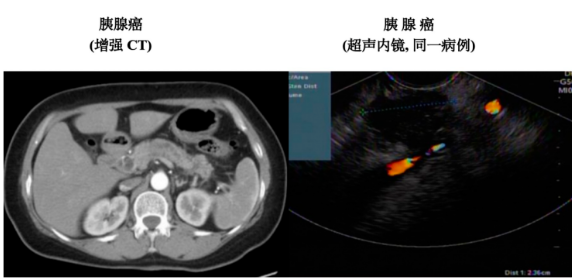

胰腺癌因早期症状隐匿、恶性程度高,被称为“癌中之王”,而早期诊断是改善预后的核心。腹部超声、CT、核磁、超声内镜(EUS)、逆行性胰胆管造影(ERCP)、病理学诊断等多种诊断方式的综合应用,是早期诊断胰腺癌的主要手段。超声内镜凭借独特优势,成为胰腺癌诊断中不可或缺的“精准武器”。

超声内镜结合内镜和超声技术,通过内镜将高频超声探头送入消化道,对胰腺进行近距离扫描。这种技术能突破传统超声受胃肠道气体、腹壁脂肪的干扰,清晰显示胰腺细微结构,甚至发现微小肿瘤,助力早期胰腺癌的检出。